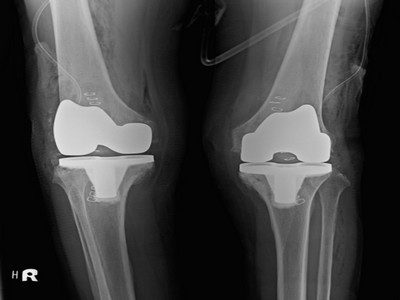

孫女士於六月底抵達花蓮慈院,經由x光檢查報告,確定孫女士的雙膝蓋嚴重磨損。陳英和表示,一般膝蓋在健康情況下,頂端會呈現圓弧狀,但孫女士的則已磨平,加上退化性關節炎長久下來,會導致關節變形,原本腳型正常的人就有可能變成O型腿,孫女士的雙腿已經呈現向外彎曲約二十度。

圖:術前術後x光報告比對圖。左圖為術前,健康膝蓋頂端會呈現圓弧狀,孫女士的則已嚴重磨損、磨平,且雙腿呈現向外彎曲約二十度O型腿狀;右圖為孫女士接受「微創式人工膝關節置換手術」後的雙膝狀況。